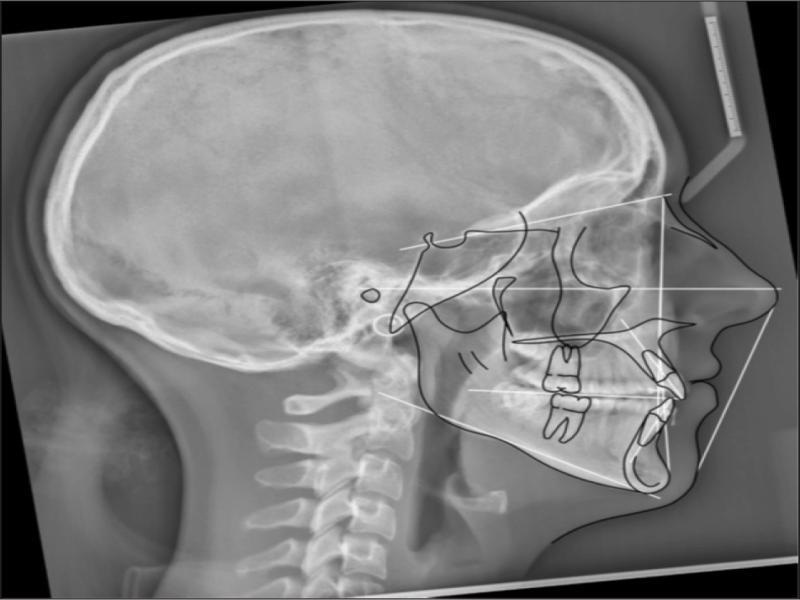

A radiographic examination was unremarkable on the OPG (Figure 2). Cephalometrically (Figure 3, Table I) a Class III skeletal relationship was evident, with a Wits discrepancy of -2.1 mm (due primarily to maxillary retrusion – SNA 72.6°). However, the Class III was camouflaged by the significant vertical disproportion, highlighted by an increased mandibular plane angle (28.6°), reduced facial axis angle (83.2°), reduced Jarabak’s ratio (56.5%), and increased lower anterior facial height (53.4%), all of which indicated a dolichofacial pattern. The maxillary retrusion, combined with a mandibular downward and backward rotation, resulted in a bimaxillary retrusive skeletal relationship (SNB 72.6°). The upper incisors were at an acceptable angulation relative to the palatal plane (112°) and the anteroposterior position relative to Na-Vert. The lower incisors were at an acceptable position relative to APo but were retroclined relative to the mandibular plane (80.7°) according to mesofacial norms.

Pretreatment lateral cephalogram.